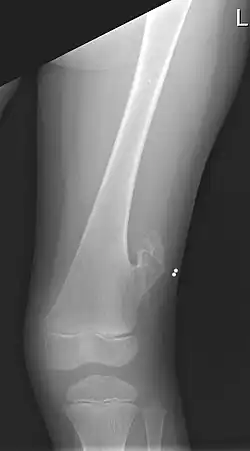

![]() Рентген левого бедра 5-летнего мальчика с экзостозом, расположенным латерально, чуть выше колена. | |

Экзостоз (также используется название костная шпора) — доброкачественное образование новой костной ткани на поверхности кости[3]. Экзостозы могут вызывать хроническую боль от легкой до сильной, в зависимости от формы, размера и места поражения. Чаще всего они встречается в районе рёбер, где образуются небольшие костные наросты, но иногда более крупные наросты могут образовываться в таких местах, как лодыжки, колени, плечи, локти и тазобедренные суставы. Изредка они появляются на черепе.